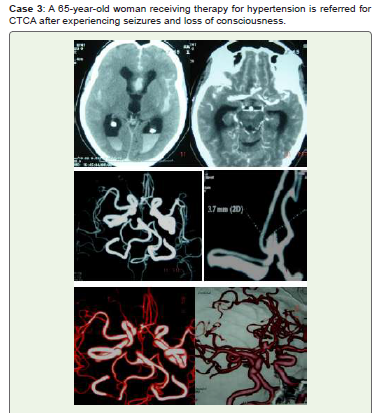

Figure 3:Noncontract CT (A) reveals intraventricular hemorrhage in the

posterior horns of lateral ventricles as well as acute SAH in Sylvian fissures,

interhemispheric fissures, and along cerebral sulci. Anterior communicating

artery (ACOM) saccular aneurysm is visible on CTCA (B), MIP (C, D), and

3D-VR (E, F) images. During conservative treatment, the patient passed away.